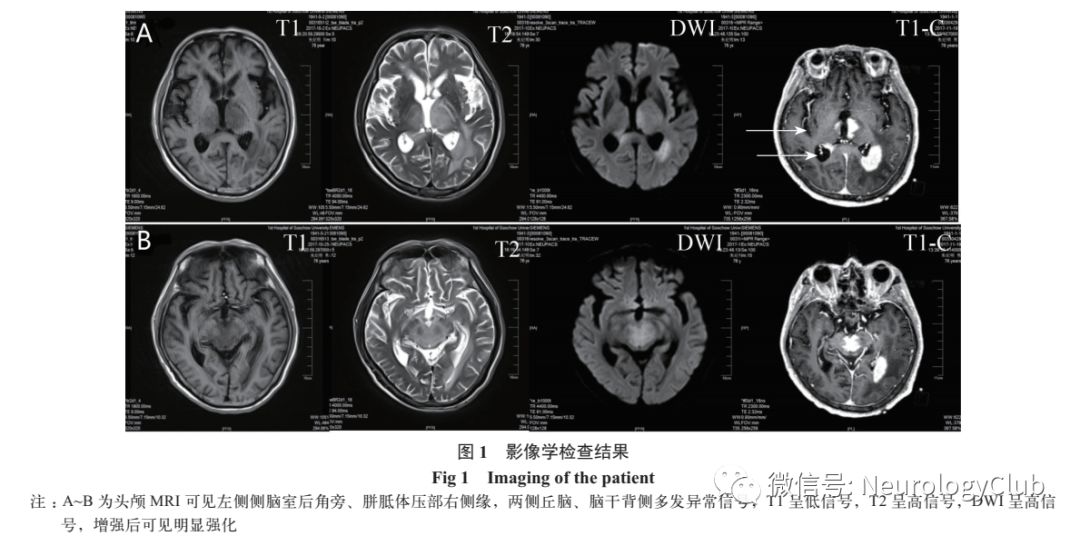

影像学检查  ①头颅磁共振成像(MRI):左侧侧脑室后角旁、胼胝体压部右侧缘,两侧丘脑、脑干背侧多发异常信号影,增强后明显强化(图1)。②头颅CT+CTA+CTV:CT平扫示左侧侧脑室后角旁、胼胝体压部右侧缘,两侧丘脑、脑干背侧多发高密度影;CTA示左颈总动脉颈段、左颈外动脉起始处混合斑块,管腔中度狭窄;CTV未见明显异常。③胸腹盆腔CT平扫:慢支、肺气肿,两肺散在炎症,左肺下叶小结节,双侧胸腔积液;全腹部平扫未见明显异常。甲状腺超声:未见明显异常。

病史小结  患者为76岁男性,头晕起病,症状进行性加重,逐渐出现意识障碍、视物重影、肢体乏力症状。脑脊液检查示白细胞和蛋白升高。头颅MRI可见病灶主要位于双侧丘脑和脑干,双侧丘脑和脑干病变常见病因(表1)。